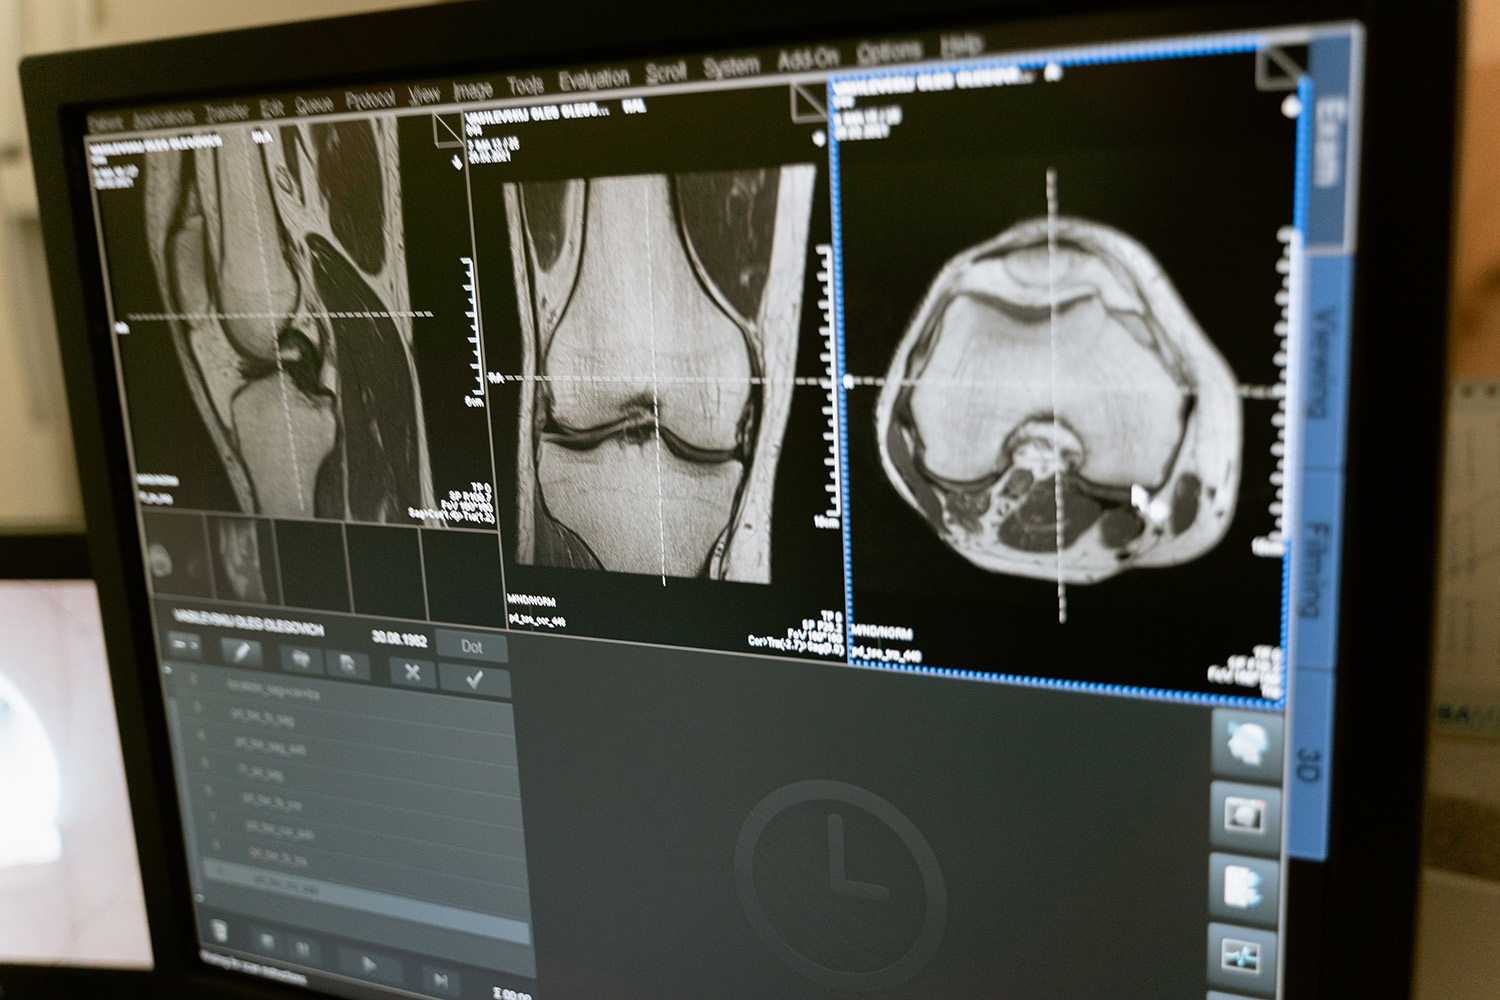

MAGNETRESONANZTOMOGRAPHIE (MRT) ZUR FRÜHERKENNUNG VON ERKRANKUNGEN AUS DEM RHEUMATISCHEN FORMENKREIS

Wie setzen wir die Magnetresonanztomographie ein, um Erkrankungen aus dem rheumatischen Formenkreis möglichst früh zu erkennen? Zu den hier durchgeführten diagnostischen Untersuchungen möchten wir Sie in diesem Beitrag informieren.

Wie bei jeder Erkrankung gilt auch rheumatischen Erkrankungen: Früh erkennen und effektiv behandeln erhöht die Erfolgschancen für den weiteren Krankheitsverlauf. Die Magnetresonanztomographie (MRT) ermöglicht die Früherkennung rheumatischer Erkrankungen und der weiteren Behandlung. Die wachsende Verfügbarkeit schneller und hochauflösender Untersuchungstechniken der Magnetresonanztomographie bei der Darstellung peripherer Gelenke bieten Patienten und Ärzten enorme Verbesserungen.

Die häufig chronischen Entzündungen finden sich meist an den Gelenkstrukturen von Händen und Füßen, oft aber auch von Sehnen, Sehnenscheiden und Bandansätze ohne knöcherne Beteiligung. In vielen Fällen sind die Symptome und Laborbefunde nicht eindeutig oder widersprüchlich.

In unseren Radiologischen Gemeinschaftspraxen in Calw und Leonberg stehen unseren Patienten aus dem gesamten Raum Stuttgart die erforderlichen Geräte und Techniken zur Verfügung, um Frühzeichen und Vorstufen einer solchen Entzündung aufzudecken, bevor eine Schädigung der betroffenen Strukturen eingetreten ist. Bitte sprechen Sie mit Ihrem behandelnden Arzt und nehmen mit uns Kontakt auf.